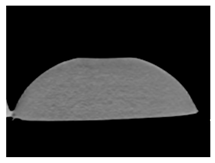

| CT-scan |  |  |  |

| CT-scan |  |  |  |

| CT-scan |  |  |  |

| CT-scan |  |  |  |

| CT-scan |  |  |  |

| CT-scan |  |  |  |